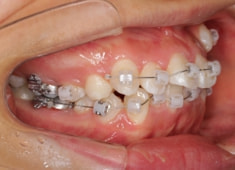

治療開始時